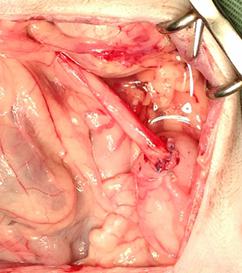

尿管切開による結石摘出

尿管移設